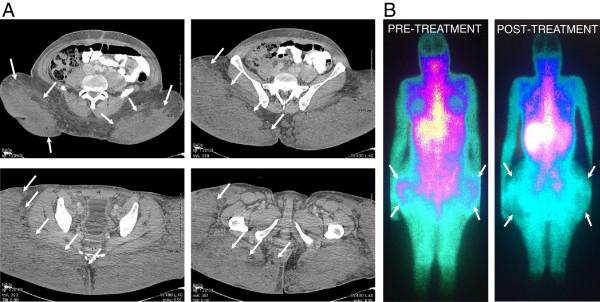

Here we describe the case of a 40-year-old African American male-to-female transgender patient who presented to our institution with hypercalcemia and acute renal failure secondary to body contouring injections with industrial strength silicone by non-licensed providers, a decade prior to her visit. Work-up revealed an extensive granulomatous inflammatory process in the injection area resulting in electrolyte abnormalities and kidney injury. The patient's lab results and symptoms responded well to long-term corticosteroid treatment and correlated with treatment adherence.

在此,我们描述一名40岁非裔美国男变女跨性别患者的病例,该患者在就诊前十年,由非持牌医疗人员使用工业强度硅胶进行身体塑形注射后,出现高钙血症和急性肾衰竭,并前来我院就诊。检查发现注射部位存在广泛的肉芽肿性炎症过程,导致电解质异常和肾损伤。患者的实验室检查结果和症状对长期皮质类固醇治疗反应良好,且与治疗依从性相关。